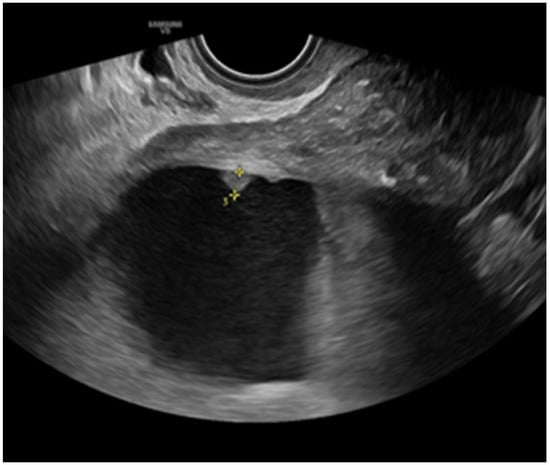

- Savelli, L.; De Iaco, P.; Ceccaroni, M.; Ghi, T.; Ceccarini, M.; Seracchioli, R.; Cacciatore, B. Transvaginal sonographic features of peritoneal carcinomatosis. Ultrasound Obstet. Gynecol. 2005, 26, 552–557. [Google Scholar] [CrossRef]

- Weinberger, V.; Fischerova, D.; Semeradova, I.; Slama, J.; Dundr, P.; Dusek, L.; Cibula, D.; Zikan, M. Prospective Evaluation of Ultrasound Accuracy in the Detection of Pelvic Carcinomatosis in Patients with Ovarian Cancer. Ultrasound Med. Biol. 2016, 42, 2196–2202. [Google Scholar] [CrossRef]

- Testa, A.C.; Ludovisi, M.; Mascilini, F.; Di Legge, A.; Malaggese, M.; Fagotti, A.; Fanfani, F.; Salerno, M.G.; Ercoli, A.; Scambia, G.; et al. Ultrasound evaluation of intra-abdominal sites of disease to predict likelihood of suboptimal cytoreduction in advanced ovarian cancer: A prospective study. Ultrasound Obstet. Gynecol. 2012, 39, 99–105. [Google Scholar] [CrossRef]

- Fischerova, D.; Zikan, M.; Semeradova, I.; Slama, J.; Kocian, R.; Dundr, P.; Nemejcova, K.; Burgetova, A.; Dusek, L.; Cibula, D. Ultrasound in preoperative assessment of pelvic and abdominal spread in patients with ovarian cancer: A prospective study. Ultrasound Obstet. Gynecol. 2017, 49, 263–274. [Google Scholar] [CrossRef]

- Tomasinska, A.; Stukan, M.; Badocha, M.; Myszewska, A. Accuracy of Pretreatment Ultrasonography Assessment of Intra-Abdominal Spread in Epithelial Ovarian Cancer: A Prospective Study. Diagnostics 2021, 11, 1600. [Google Scholar] [CrossRef]